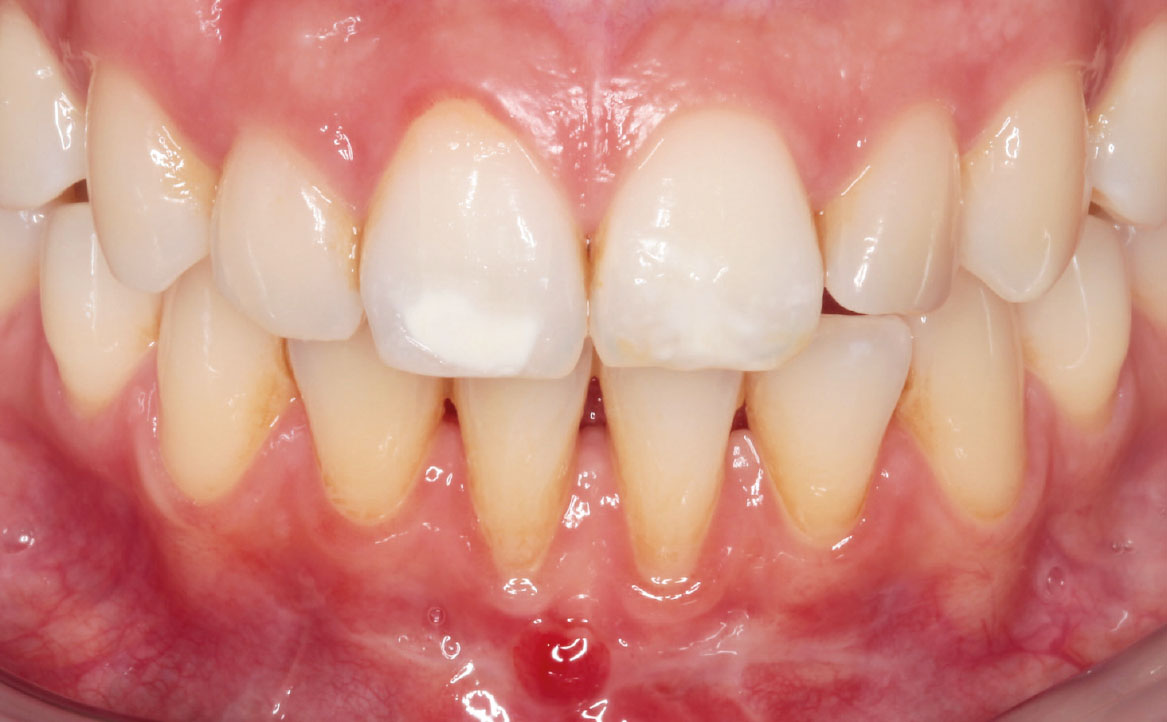

Il caso descritto riguarda una giovane paziente di 31 anni che si è presentata presso l’Unità Operativa di Odontostomatologia dell’Ospedale di Parma per recessioni gengivali di grado I di Miller della superficie vestibolare degli elementi 3.1 e 4.1. La paziente ha riferito deficit di coagulazione congenito e allergia alla mepivacaina.

All’esame obiettivo si è riscontrata scarsità della profondità del vastibolo in zona mandibolare anteriore. Si è deciso perciò di intervenire chirurgicamente eseguendo una vestibuloplastica inferiore con laser Nd:YAG.